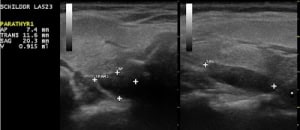

Während gesunde Nebenschilddrüsen aufgrund ihres gleichen Schallmusters wie die Schilddrüse normalerweise sonographisch nicht abzugrenzen sind, können die immer gutartigen Nebenschilddrüsenadenome per Ultraschall häufig erkannt werden.

Spezialisierte Chirurgen sind in der Lage, über einen ca. 2 cm großen Schnitt Nebenschilddrüsenadenome innerhalb weniger Minuten (in Narkose) zu entfernen. Hierfür ist allerdings erforderlich, zuvor die Lokalisation mit einer Nebenschilddrüsen-Szintigraphie abzusichern. Dafür wird in der Regel Tc-99m-markiertes MIBI injiziert, das sich in den meisten Nebenschilddrüsenadenomen anreichert. Mit dieser Methode können auch ektop gelegene Nebenschilddrüsenadenome gefunden werden.